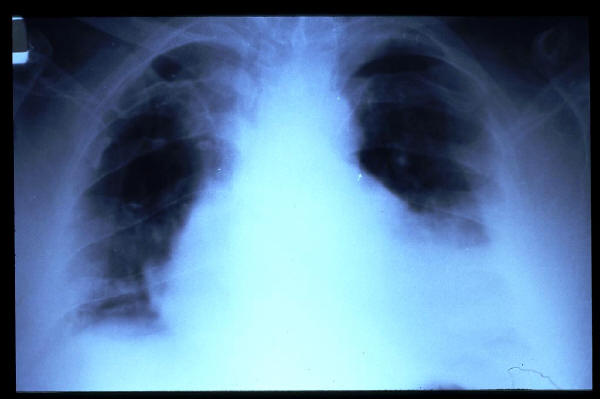

MO Distres respiratorio del adulto por trauma.